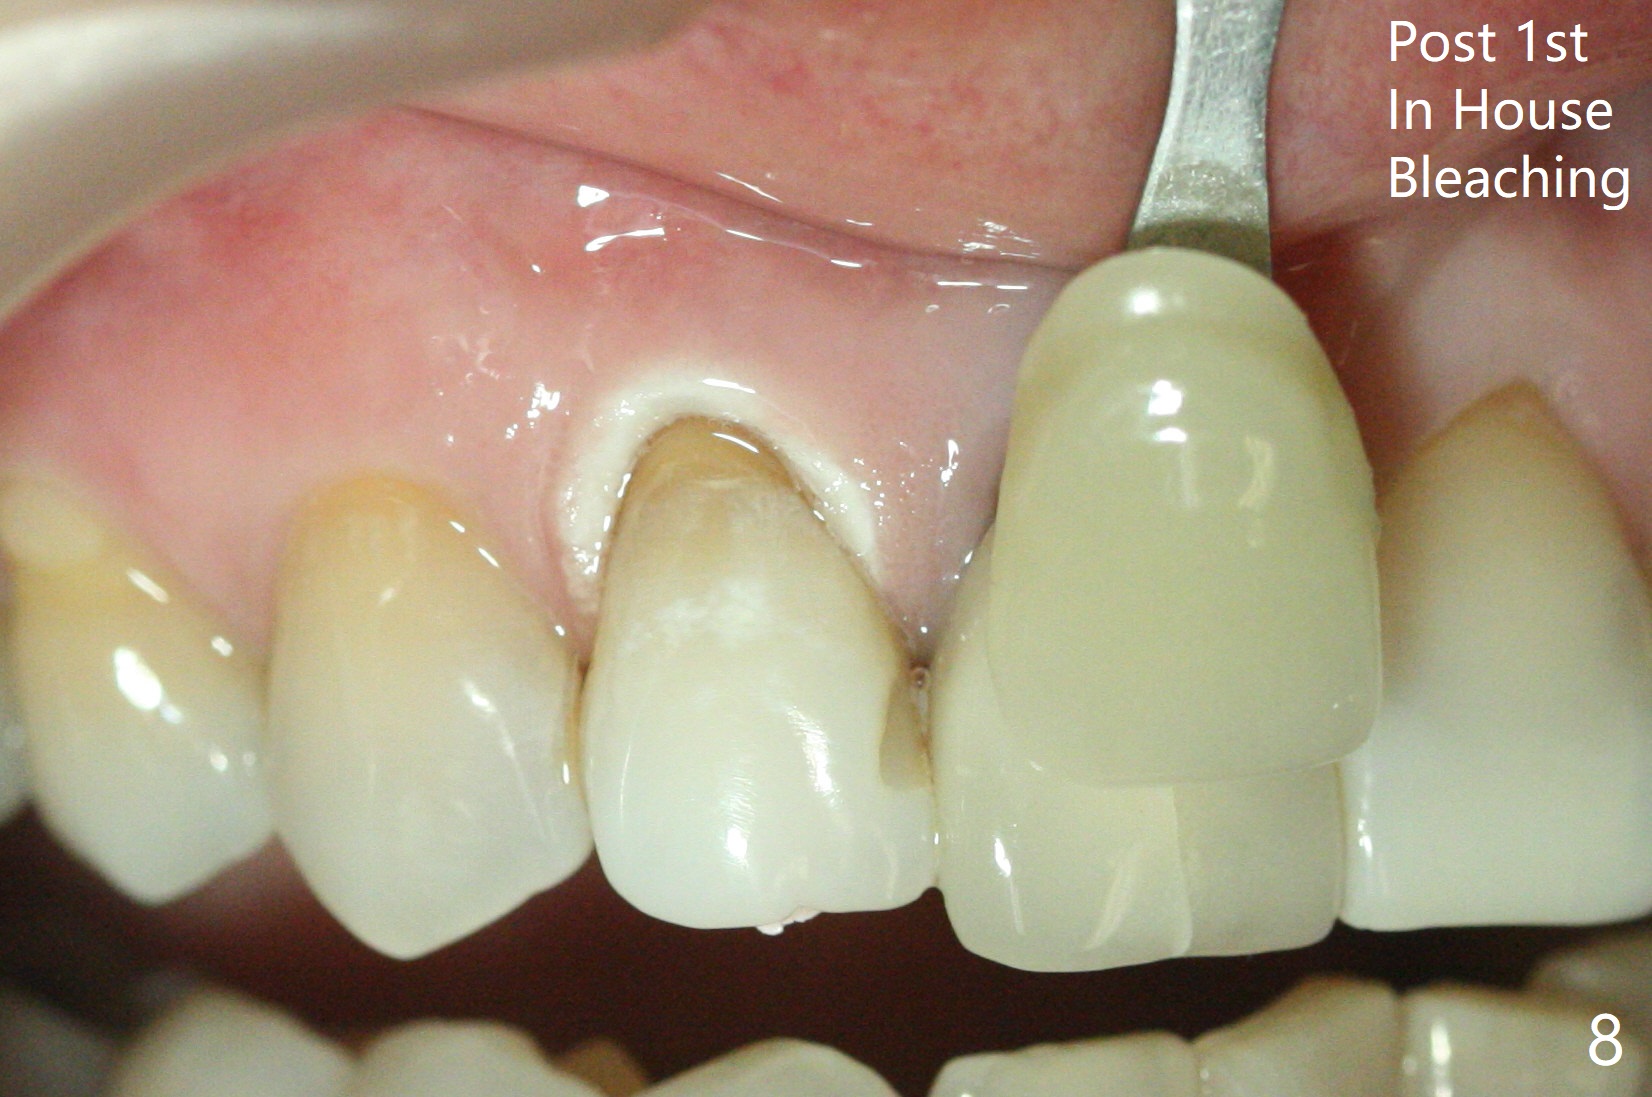

A 46-year-old woman requests a crown for the discolored tooth #7 (Fig.1,2) with mesiolingual composite (Fig.3 C) and periapical radiolucency (*). After RCT (Fig.4,5) with sodium hypochlorite, the tooth #7 is whiter than the ML composite (Fig.6,7). The patient returns 1 day post RCT for in house internal and external bleaching (Fig.8) with 35% hydrogen peroxide gel closed in the canal when she leaves. Three weeks later, the lateral incisor has the shade as the neighboring natural teeth (Fig.9,10). After the lightest shade composite placed in the canal and the access hole (Fig.11), the lateral looks better than the central with a crown and cervical discoloration (Fig.12).